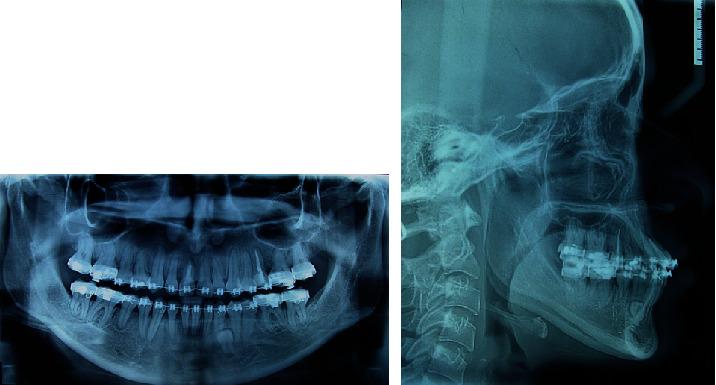

Treating skeletal class III malocclusions is one of the biggest challenges in Orthodontics. Given the complexity of these cases, orthognathic surgery is often the best treatment option. However, many patients refuse this treatment due to its risks, morbidity, and costs involved. Alternatively, dental compensation can be planned for some of these skeletal problems. This case report presents a dentoalveolar compensation in the orthodontic treatment of a 20-year-old female patient with class III malocclusion, concave profile, anterior crossbite, mandibular prognathism, maxillary retrusion, and a vertical deficiency in the posterior region. Treatment planning involved a multiloop edgewise archwire (MEAW) associated with intermaxillary elastics with counterclockwise rotation of the occlusal plane in the posterior region of the maxilla aiming at obtaining an increased posterior vertical dimension. After 24 months of treatment, the severe anterior crossbite was corrected, and the skeletal class III relationship was camouflaged. At the end of the orthodontic treatment, it was possible to observe an improved facial profile, a nice smile, and a functional occlusion. The results remained stable at a three-year follow-up. The MEAW, associated with the use of elastics, seems to be an effective treatment option for class III camouflage with reduced posterior vertical dimension with no need for additional anchoring devices but requiring adequate bending of wires and patient compliance.

治疗骨性III类错牙合畸形是正畸领域最大的挑战之一。鉴于这些病例的复杂性,正颌手术往往是最佳治疗选择。然而,许多患者因手术风险、发病率和费用而拒绝这种治疗。另外,对于其中一些骨骼问题可以考虑进行牙代偿。本病例报告介绍了一名20岁III类错牙合畸形女性患者的正畸治疗中的牙牙槽代偿情况,该患者面部凹陷、前牙反牙合、下颌前突、上颌后缩且上颌后部垂直高度不足。治疗计划包括使用多曲方丝弓(MEAW)并配合颌间弹力牵引,使上颌后部牙合平面逆时针旋转,旨在增加上颌后部垂直高度。经过24个月的治疗,严重的前牙反牙合得到矫正,骨性III类关系得以掩饰。正畸治疗结束时,面部轮廓改善、笑容美观且咬合功能良好。三年随访时结果保持稳定。MEAW配合弹力牵引似乎是一种有效的治疗方法,可用于掩饰垂直高度降低的III类错牙合畸形,无需额外的支抗装置,但需要对弓丝进行适当弯制并要求患者配合。